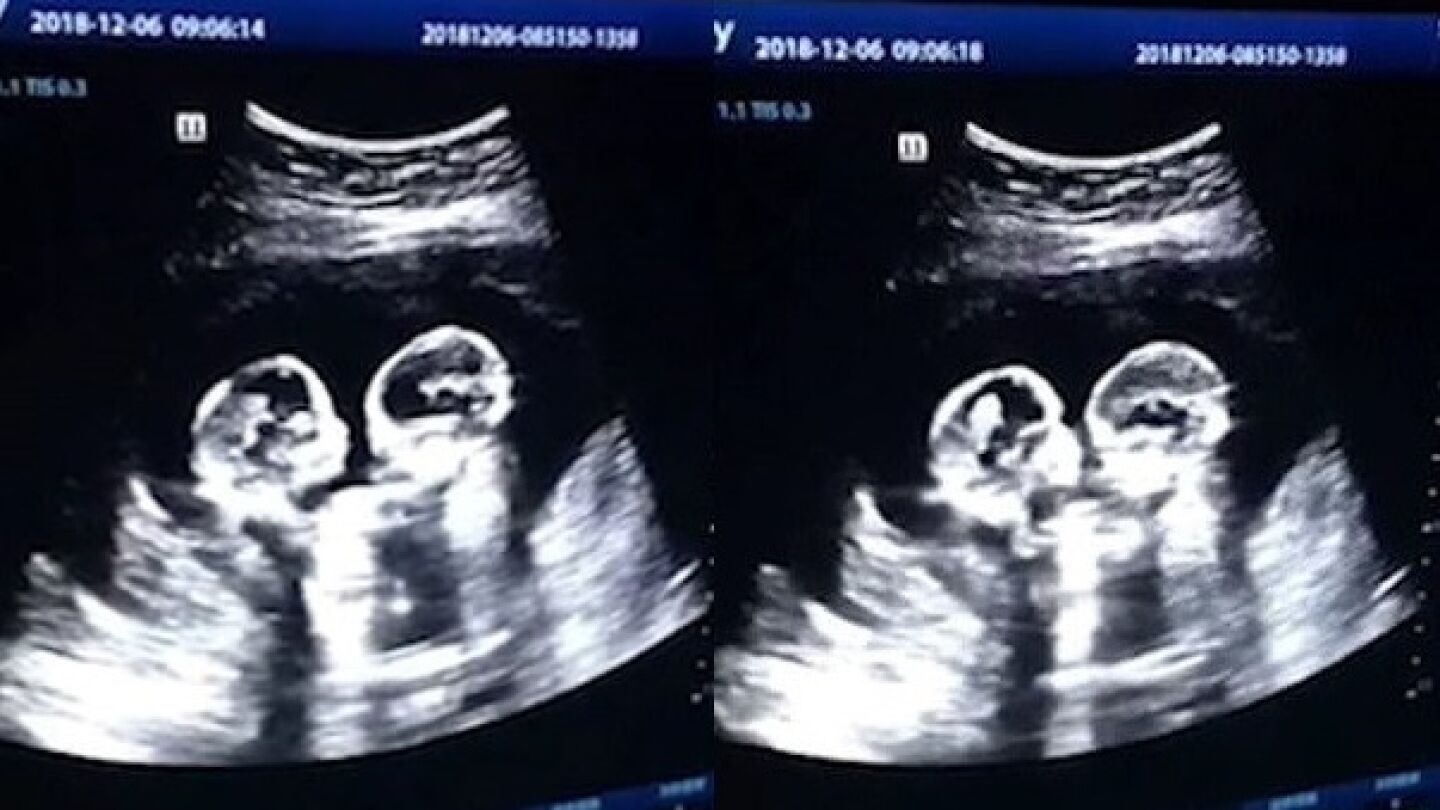

En Yinchuan, China, dos gemelas fueron grabadas el pasado diciembre 'peleándose' dentro del útero durante una revisión en el cuarto mes de gestación, según ha recogido el 'China Daily'.

La ecografía reveló cómo las dos hermanas comenzaban a darse 'patadas' y 'golpes' en el interior de la barriga de su madre.

Las imágenes fueron captadas por el padre de las criaturas, quien se quedó sorprendido ante tal escena. No obstante, según el señor Tao no era la primera vez que veía a las niñas interactuando entre ellas durante una ecografía.

Las gemelascompartían el mismo saco amniótico (gemelos monoamnióticos) por lo que el embarazo era raro y además de alto riesgo. No obstante tenían un 50% de posibilidades después de las 26 semanas y así lo han hecho.